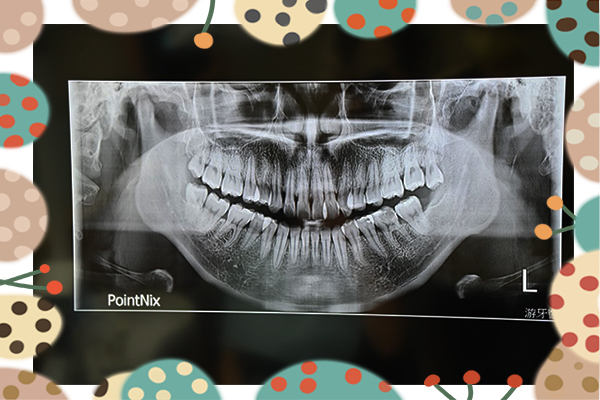

來到游牙醫做牙齒矯正一定會做的一件事就是拍x光,朱醫師說:首先牙齒矯正最重要就是先觀察牙齒生長狀況,如何正確評估將牙齒導正是每位牙齒矯正醫師的基本功!